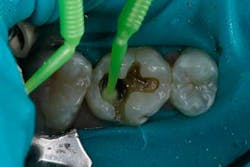

The tooth was prepared and a total etch technique utilizing 37% phosphoric acid was performed (Figs. 3 through 5). After the etchant was rinsed, a desensitizer was placed and blotted to leave a moist dentin surface for bonding (Fig. 6). The bonding agent was applied; the ethanol solvent was air evaporated using a warm air dryer; and the adhesive light-cured for 10 seconds (Figs. 7 and 8).

Fig. 6.